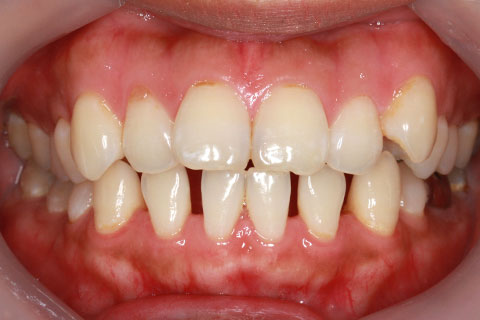

治療前

治療中(開始直後)

治療中(開始半年後)

治療後

- 年齢・性別

- 25歳女性

- 治療期間

- 2年0ヶ月

- 抜歯

- 上下4番抜歯

- 治療費

- 110万円

- 表側矯正と比較して、力学的な操作性が複雑なため、ボーイングエフェクトを起こしやすい。